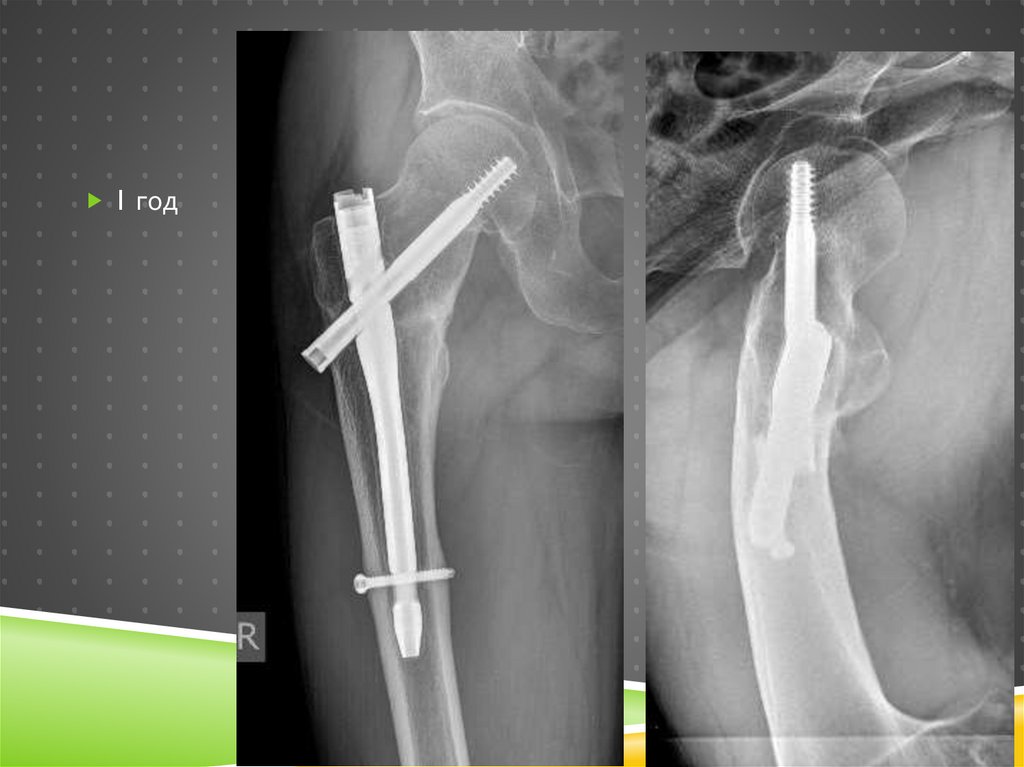

Через год